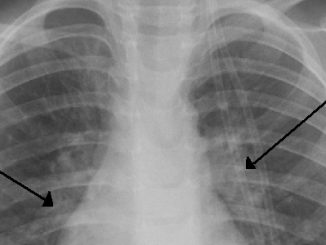

Selon la revue médicale Prescrire publiée lundi, la kinésithérapie respiratoire n'est pas efficace pour traiter la bronchiolite, une infection respiratoire qui touche en hiver presque 30 % des enfants de moins de deux ans et elle pourrait entraîner des effets gênants tels…